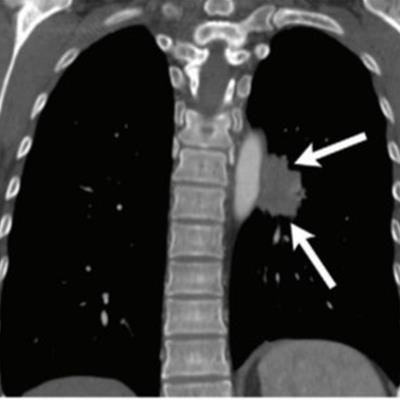

Images in a 52-year-old woman with a 10 pack-year history of smoking. (a) Initial chest radiograph shows a 2.4-cm nodule (arrow) overlapped by left hilar shadow. This lesion was undetected on the original report. (b) The deep learning-based automatic detection algorithm (DLAD) correctly detected this lesion with a probability value of 35%. Without DLAD, only two observers correctly detected the lesion; however, with DLAD, all nine observers detected the lesion and recommended chest CT for further evaluation. (c) Follow-up chest radiograph at time of diagnosis shows interval increase in lesion (arrows). (d) Follow-up chest CT image at time of diagnosis shows enhancing mass in left lower lobe (arrows). Patient was diagnosed with stage IV lung adenocarcinoma as bone metastasis was observed. The time between the initially overlooked chest radiograph and pathologic diagnosis was 447 days. Images and caption courtesy of the RSNA.

Images in a 52-year-old woman with a 10 pack-year history of smoking. (a) Initial chest radiograph shows a 2.4-cm nodule (arrow) overlapped by left hilar shadow. This lesion was undetected on the original report. (b) The deep learning-based automatic detection algorithm (DLAD) correctly detected this lesion with a probability value of 35%. Without DLAD, only two observers correctly detected the lesion; however, with DLAD, all nine observers detected the lesion and recommended chest CT for further evaluation. (c) Follow-up chest radiograph at time of diagnosis shows interval increase in lesion (arrows). (d) Follow-up chest CT image at time of diagnosis shows enhancing mass in left lower lobe (arrows). Patient was diagnosed with stage IV lung adenocarcinoma as bone metastasis was observed. The time between the initially overlooked chest radiograph and pathologic diagnosis was 447 days. Images and caption courtesy of the RSNA.Using AI with chest radiography could go a long way to improve patient care, the team concluded.